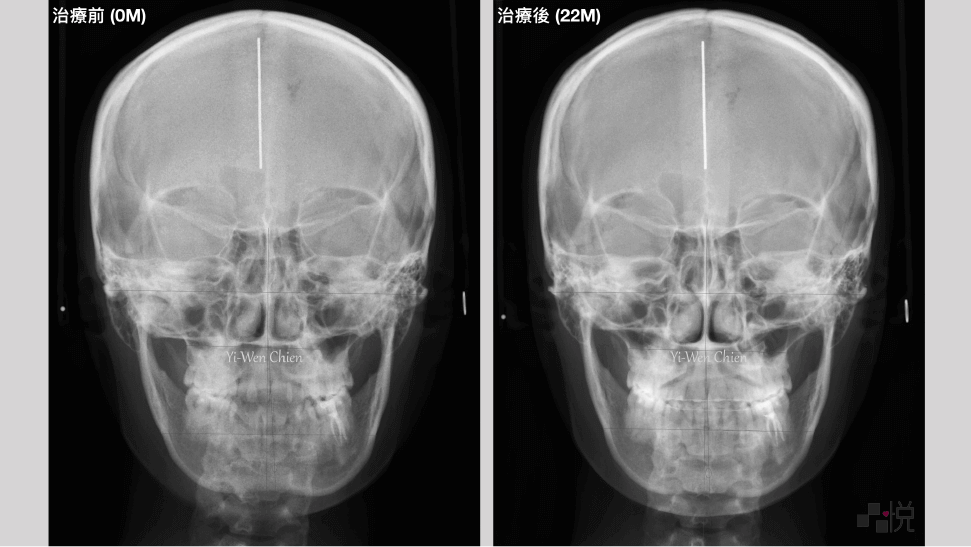

本案例治療前有輕微的「骨性戽斗」,齒列擁擠,上顎及下顎中線偏差,合併有前牙和後牙錯咬,而後牙錯咬造成了咬合干擾,使得下顎往右側歪斜。

採用不拔牙的矯正治療,並且讓下顎順時針旋轉改善戽斗的外觀。牙齒矯正後咬合干擾消失,同時改善臉部歪斜。